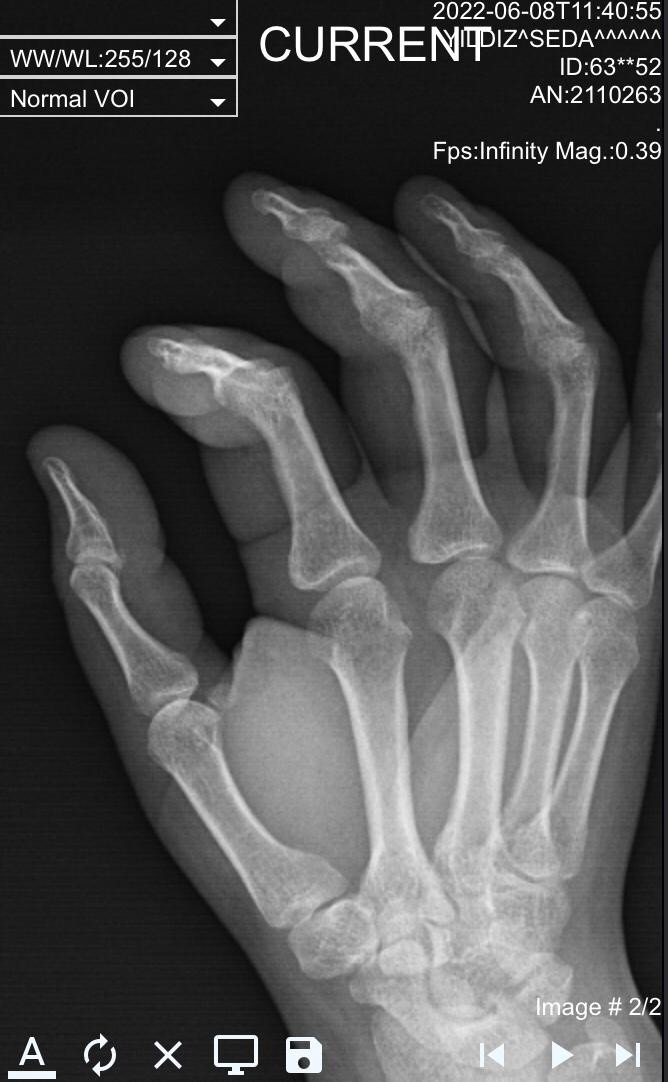

Kavgaya karışan komşusunun tüm aile fertlerini ayırıp sakinleştirmek isterken şiddete maruz kalan Mustafa Y., "Eşim, dışardan ses geldiğini bir bakmamı söyledi. Çıkıp baktığımda komşumun kayınbiraderi ile kavga ettiğini, birbirlerine girdiğini görüp ayırmaya çalıştım. Ayırdım, o sırada komşumun kayınpederi yukarıdan geldi ve önce oğluna vurdu. Ben onu da ayırdım sonra kızına vurmaya çalıştı. Sinirli olduğunu görünce sakinleştirmeye çalıştım. Oğlu için "evladındır, vurma" dedim. Çünkü herkes toplanmıştı buraya. Tam aşağıya inecektim ki tokat attı, yumrukladı ve itekledi. Daha sonra kafamı asansöre çarptım. O sırada eşim buradaydı. Hamile olduğu için içeriye götürmeye çalıştım. Telefonu alıp 112'yi aramak için içeriye girdim. Eşimin komşumun kayınpederine, "biz buraya kavga etmeye değil, ayırmaya geldik" dedikten sonra kolunu arbede sırasında çevirdiğini söyledi. Polis ekiplerine durumu anlatarak hastaneye gittik darp raporu aldık. Hamile olduğu için film çekilmenin sakıncalı olduğunu ve sabah ortopedi doktorunun görmesini söylediler. Sonra şikayetlerimizi yapıp geldik. Sabah ortopedi doktorunun çektiği filmde eşimin parmağının kırık olduğuna dair rapor aldık ve adli makamlara sunduk" diye konuştu.